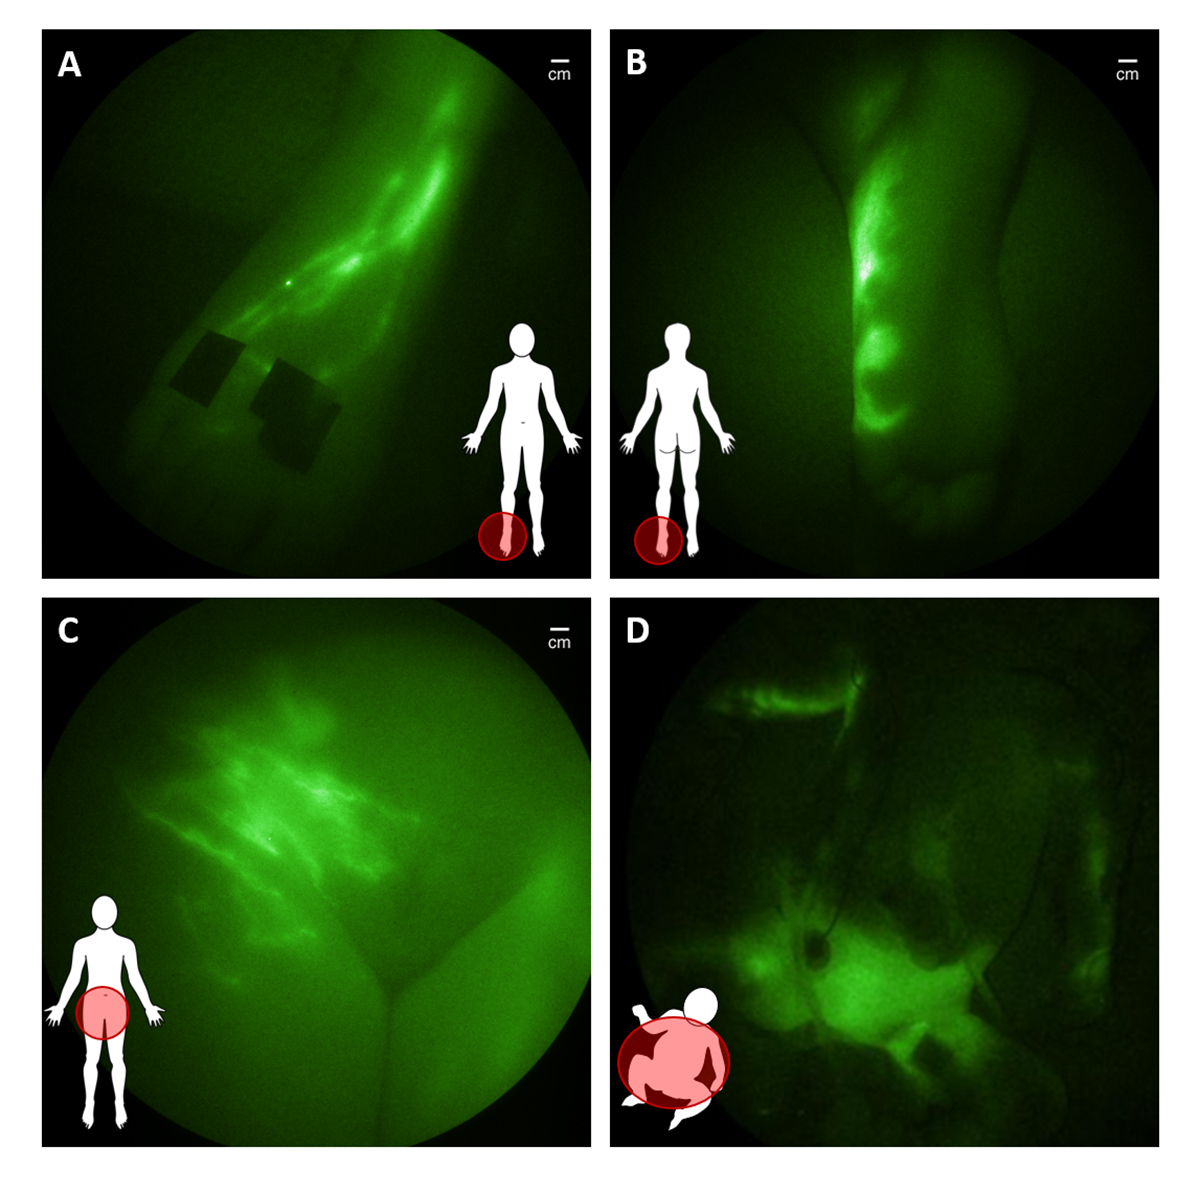

In translational studies funded in part by the National Institutes of Health and conducted under investigational new drug applications from the FDA, we have used the NIRF technology to dynamically image the lymphatics of over 400 subjects, including 30 infants and children. The imaging begins with an intradermal injection of 0.05- 0.1 mL of saline containing microgram amounts of ICG into the region of interest. ICG administration on the top of the foot results in immediate uptake into the main conducting vessels (Figure 2A) that proximally “pumps” ICG-laden lymph into the inguinal nodes before entering the central lymph channel that collects mesenteric and peripherally generated lymph for its return to the hemovascular system.

In children and adults with suspected lymphatic dysfunction, we have observed abnormal lymph drainage to the bottom of feet (Figure 2B), as well as pelvic, lymphatic congestion which in adolescents and young adults is associated with lower extremity lymphedema (Figure 2C) and, in some infants, with surgery-induced chylothorax (Figure 2D).